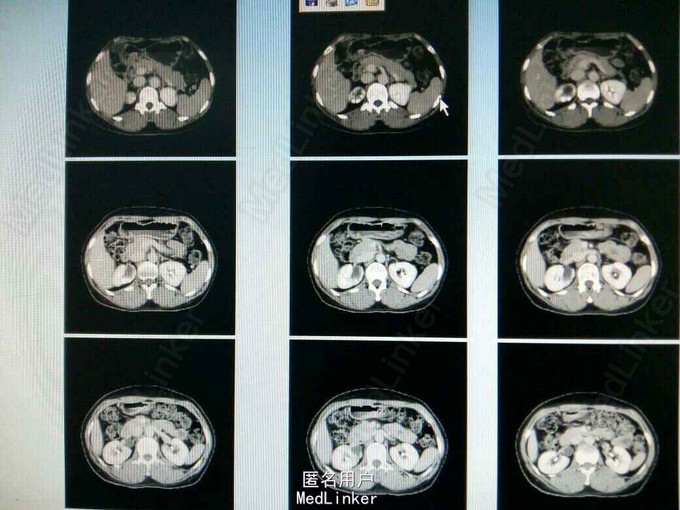

患者,女,51岁,因排尿不适来我院行B超检查发现右侧输尿管口囊肿。

ct提示右侧双肾输尿管畸形,输尿管囊肿。总肾功能正常,尿常规正常,未发现结石等异常,右上位肾脏及输尿管扩张。